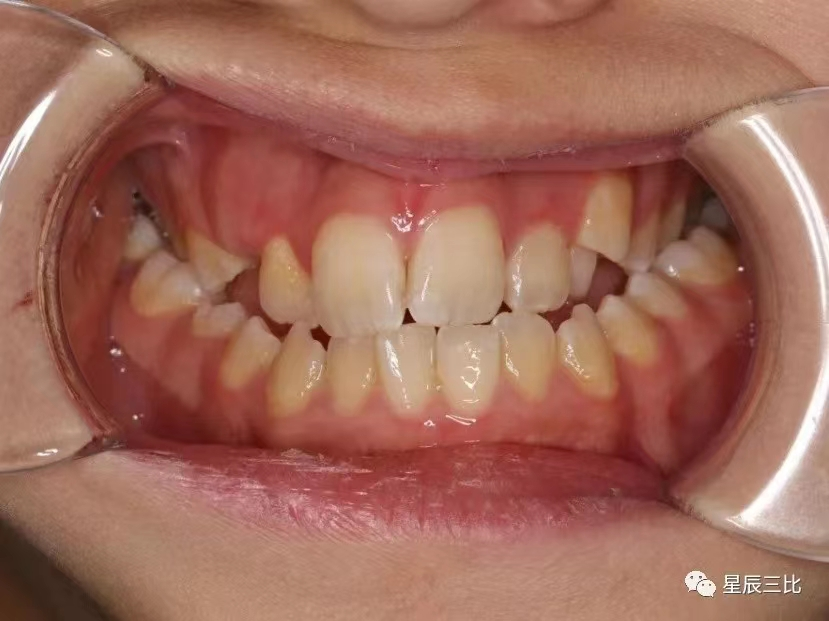

前牙反颌

“地包天”又称前牙反颌,是较为常见的牙齿颌面畸形,前牙反颌的患者外观形象大打折扣,同时咀嚼功能大幅度降低,其表现通俗来讲就是下前牙位于上前牙的外侧。